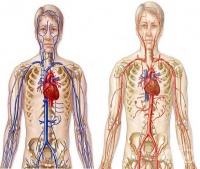

S25 Травма на кръвоносните съдове на гръдния кош

Честотата на травми на медиастиналните съдове сред преживелите тежка гръдна травма е 1,4-5%. Пострад...

S25.0 Травма на торакалната част на аортата

Евентуална повреда, на тази част на аортата, която се намира в гръдната кухина се нарича травма на т...

S25.1 Травма на безименната или подключичната артерия

Травма на безименната или подключичната артерия е рядко срещана травма, но трудна за управление. Тра...

S25.2 Травма на горната vena cava

Травма на горната vena cava най-често се получава при проникваща травма и по-рядко при високо скорос...

S25.3 Травма на безименната или подключичната вена

Травма на безименната или подключичната вена може да се причини от проникваща травма или да бъде ятр...

S25.4 Травма на белодробни кръвоносни съдове

Травмите на белодробни кръвоносни съдове са редки и изключителни трудно лечими. Най-често травма на ...

S25.5 Травма на междуребрени кръвоносни съдове

Тъпа гръдна травма може да доведе до артериално или венозно кървене, изискващо оперативно лечение ил...